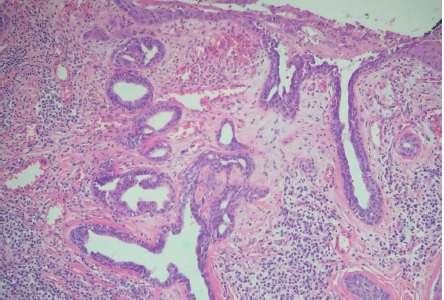

Paciente do sexo feminino, 65 anos, parda, queixando-se de prurido no couro cabeludo há um mês. Ao exame observava-se na região occipital: placa verrucosa, discretamente eritematosa medindo cerca de 2,5cm no seu maior eixo (Figuras 1 e 2). Segundo a paciente, desde o nascimento apresentava lesão assintomática no couro cabeludo que, há um mês, tornara-se pruriginosa. Optou-se por biópsia incisional da lesão e exame histopatológico, o qual evidenciou carcinoma basocelular nodular (Figura 3). Realizada então a excisão completa da lesão com margem, cujo exame histopatológico revelou: nevo sebáceo associado a siringocistoadenoma papilífero, adenoma tubular apócrino, triquilemoma (Figuras 4 a 7) e fibrose dérmica cicatricial.

O NSJ, conhecido também como nevo organoide, é mais incidente no couro cabeludo, podendo apresentar-se na face e menos comumente nos membros.3,5 Ocorre em aproximadamente 0,3% dos indivíduos, sem predileção por gênero. A lesão em geral está presente ao nascimento e apresenta-se como placa bem delimitada constituída por múltiplas pápulas confluentes de coloração amarelo-alaranjada ou amarelo-acastanhada, predominantemente no couro cabeludo, onde cursa com alopecia no local da lesão.3 Apresenta distribuição bimodal: durante a puberdade, quando sua superfície torna-se espessada e verrucosa por estímulos hormonais aos componentes écrinos e apócrinos, podendo, na fase adulta, a lesão se tornar nodular com a ocorrência de ulcerações e crostas. A possibilidade de surgimento de neoplasias secundárias nessa fase varia de dez a 30%, sendo as principais o carcinoma basocelular, o siringocistoadenoma papilífero (ambos observados nessa paciente) e o tricoblastoma.3